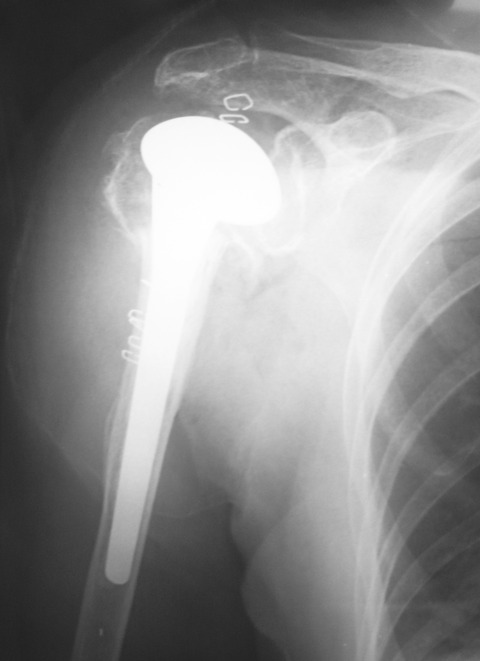

先日、高齢者の上腕骨近位端骨折(4 part骨折)に対して、右肩関節人工骨頭置換術(HHR)を施行しました。上腕骨関節面が翻転していたので、骨接合術の適応は無いと判断しました。